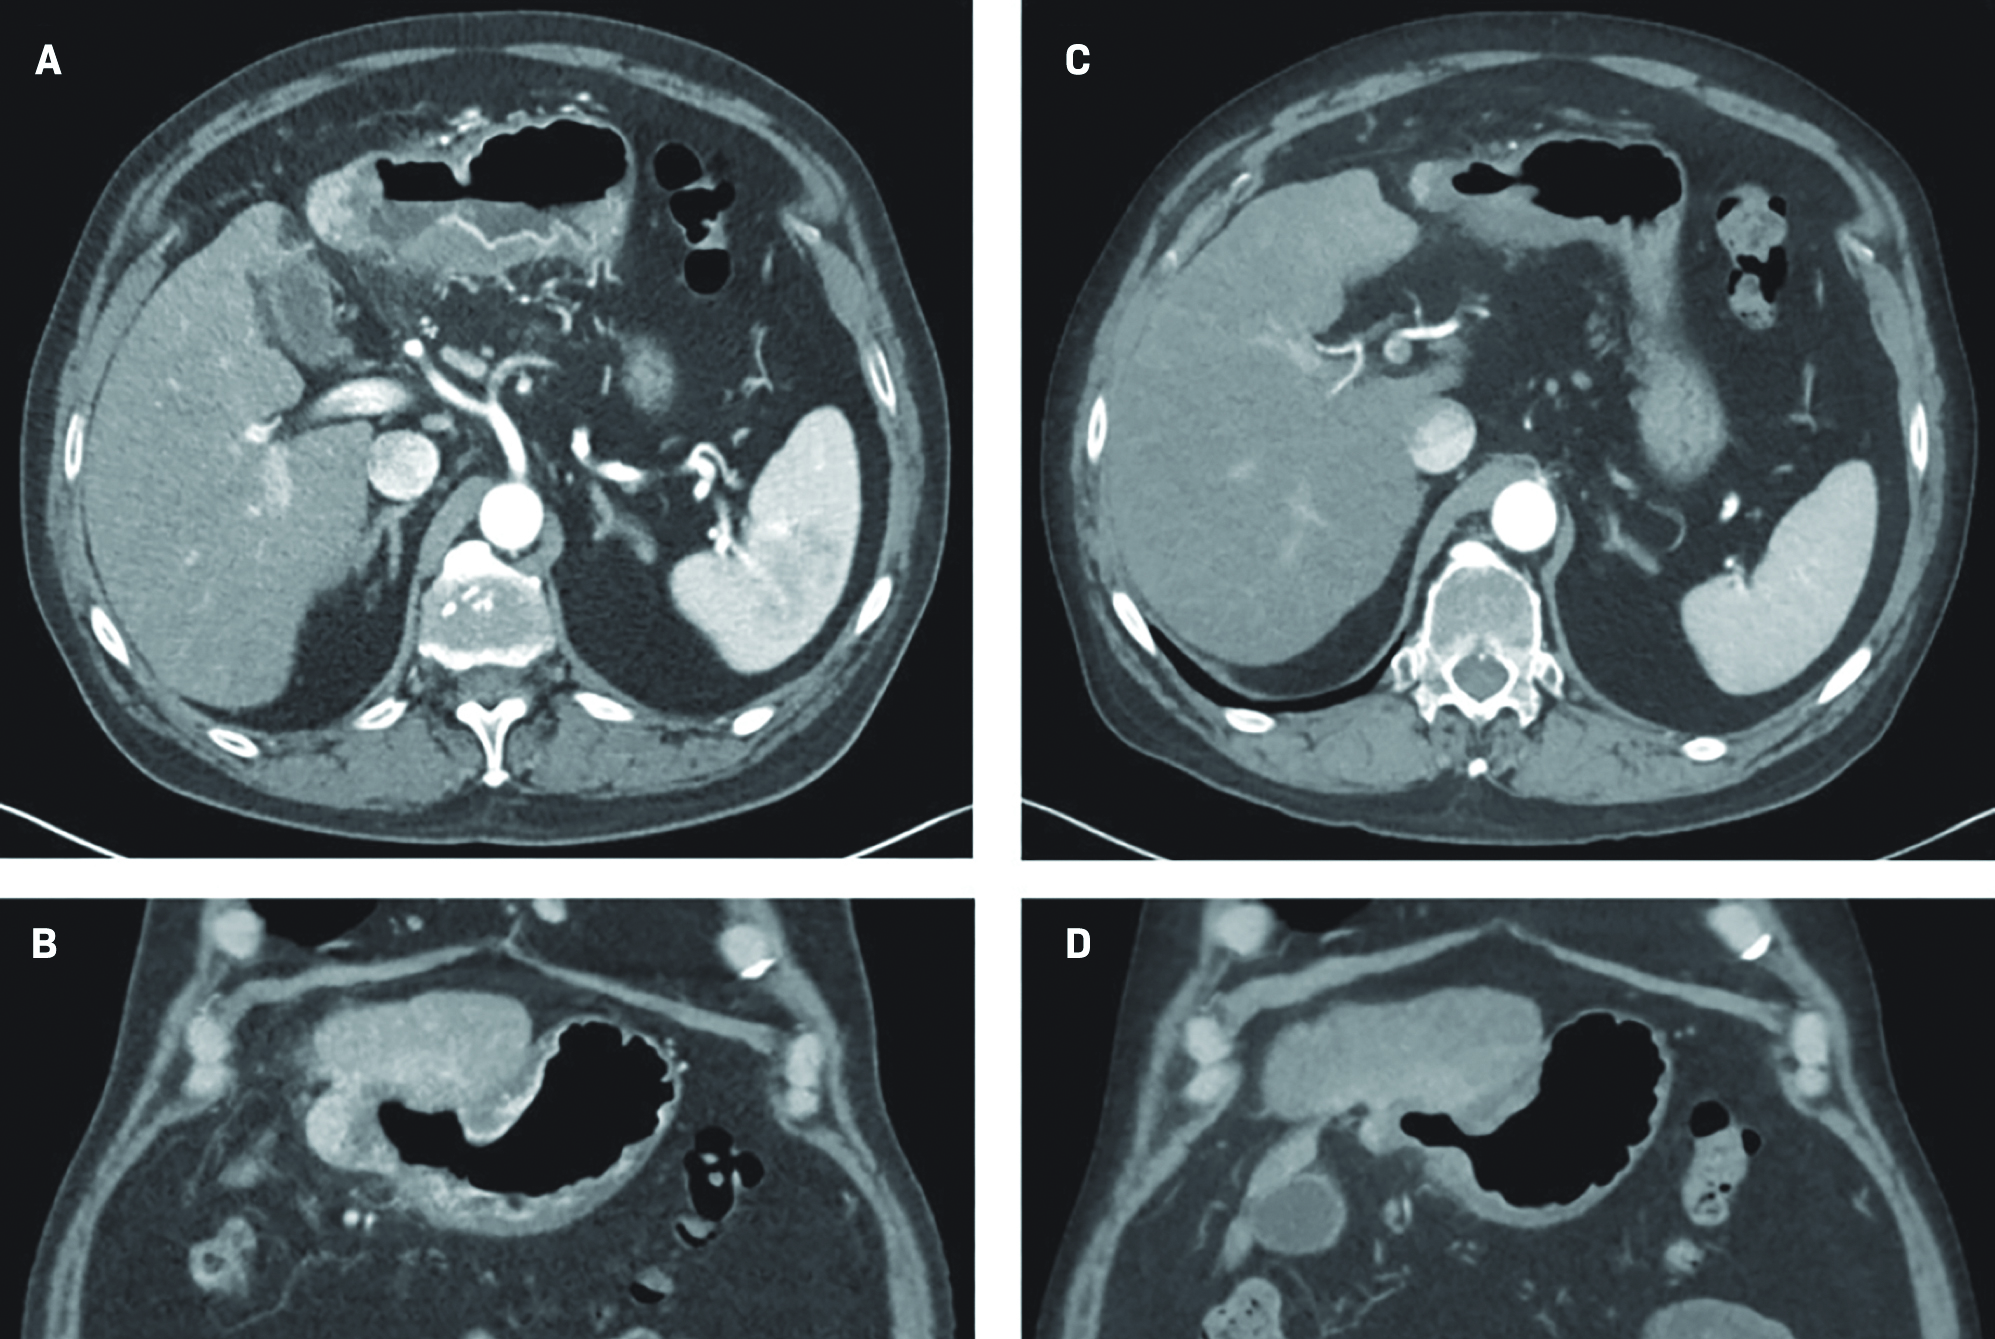

The results of the triple-phase CT at the 3-month follow-up were consistent with gastric wall invasion and fistulization (Figure 3). The fistula appeared to be asymptomatic, and close observation was pursued after review with a surgical oncologist. The patient was recently placed on a proton pump inhibitor (PPI) therapy with his primary care provider and was advised to continue this medication.

At the 6-month follow-up, the patient reported feeling well, the abdominal examination was without abnormality, and the lab work revealed an alpha-fetoprotein (AFP) value of 16.1 ng/mL. A repeat triple-phase CT of the abdomen demonstrated continual decrease in size of the treated segment 2/3 left hepatic lobe mass, with an internal air-fluid level, and stable fistulization to the stomach that measured 2.1 × 3.4 cm (Figure 3). The soft-tissue thickening of the involved stomach wall was not significantly changed. There was an interval increase in size of a new arterial-enhancing segment 4A lesion, now measuring 2.2 × 2.6 cm, likely suggestive of disease progression.